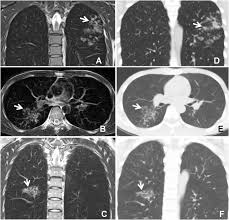

Mri Evaluation Of Pulmonary Lesions And Lung Tissue Changes Induced By Tuberculosis International Journal Of Infectious Diseases